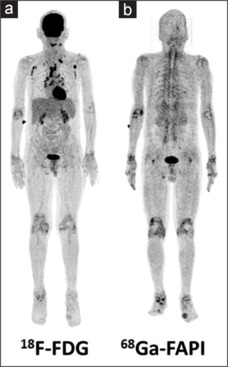

Molecular imaging findings with 18F-FDG and 68Ga-FAPI PET/CT in a case of chronic polyarthralgia.

Positron emission tomography (PET) with 18F-fluorodeoxyglucose for detection of active inflammation is well documented; however, the in vivo visualization of immune-mediated tissue remodeling has not been possible till date. With the recent development of 68Ga-fibroblast activation protein inhibitors (FAPI), which specifically binds to the activated fibroblasts located around the synovium allowing for the visualization of mesenchymal and stromal activation process in vivo, it is possible to use this modality to use as an objective indicator of disease activity. We observed increased FAPI uptake around all the large joints of the bilateral upper and lower limbs of a chronic polyarthralgia patient. In view of the specificity of FAPI for the activated fibroblasts, the possibility of future therapeutic approach using FAPI must, therefore, be kept in mind.